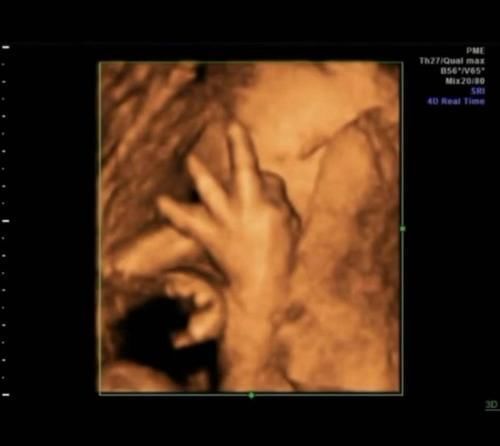

当受精卵缓慢发育成胎儿时,神经和各种器官发育缓慢。因此,当胎儿是第一个人类时,它已经有睡眠,但是在早期阶段,睡眠时间更长,这时胎儿需要的睡眠越来越少,此时胎儿的运动会越来越频繁。

许多怀孕的母亲在进行4D拍摄时发布了自己的照片,发现婴儿的动作“奇妙”,有些会“食指”,有些在“笑”,并且婴儿在玩脐带。当然,这是正常现象。